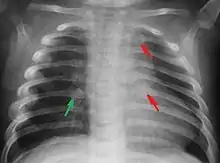

Fractures

Les enfants physiquement maltraités peuvent souffrir de fractures, particulièrement aux côtes[11].

Syndrome du bébé secoué. Secouer un bébé est une forme commune de maltraitance enfantine qui peut résulter à des dommages neurologiques irréversibles (80 % des cas) ou la mort (30 % des cas)[49]. Ces dégâts sont le résultat d'une hypertension intracrânienne (pression élevée dans le squelette) après une hémorragie interne cérébrale, des dégâts à la moelle épinière et au cou, et de fractures des os et des côtes (Institute of Neurological Disorders and Stroke, 2007).